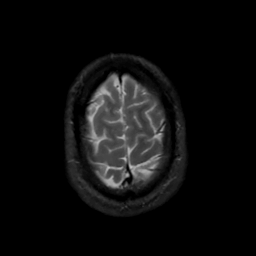

MR Study #8, March 31, 1991 -- Slice #44

[Home][Help][Clinical][Tour 1][Tour 2] Slice 44